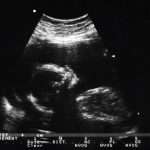

Hoy en día, todas ellas pueden ser prevenidas por el Test de Compatibilidad Genética (TCG), que permite detectar 4.500 mutaciones vinculadas a más de 600 enfermedades raras, conociendo así los genes que tiene alterados cada persona y evitando que estos sean transferidos a la descendencia.

No podemos dejar de recordar a Izan, un luchador nato que con tan solo 8 años fue diagnosticado de Adrenoleucodistrofia, y que pudo curarse de esta grave enfermedad gracias al trasplante de células madre de una de las gemelas histocompatibles con él y concebidas para poder curar a su hermano. Noa y Leire nacieron libres de la enfermedad, ya que fueron seleccionadas genéticamente mediante el Diagnóstico Genético Preimplantacional (DGP).